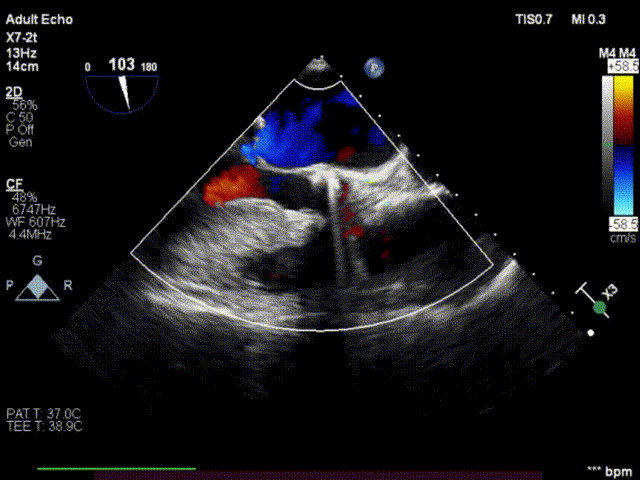

术后反流改善,无瓣周漏

术前心超

术后心超

使用28mm杰成经血管介入瓣膜,顺利完成手术,术后主动脉瓣反流情况消失。患者术后第二天便顺利出院。